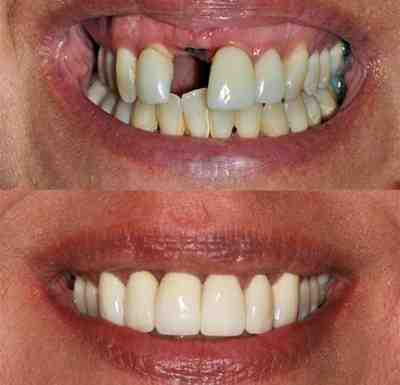

How much does a full mouth of dental implants cost

Which is better all on 4 or all on 6 dental implants?

The most obvious difference between all-in-4 and all-in-6 dental implants is the number of implants placed in the mouth. Some dentists believe that the all-in-6 dental treatment provides a stronger, more stable base for the prosthetic dental arch, resulting in a longer lasting and more pleasant smile.